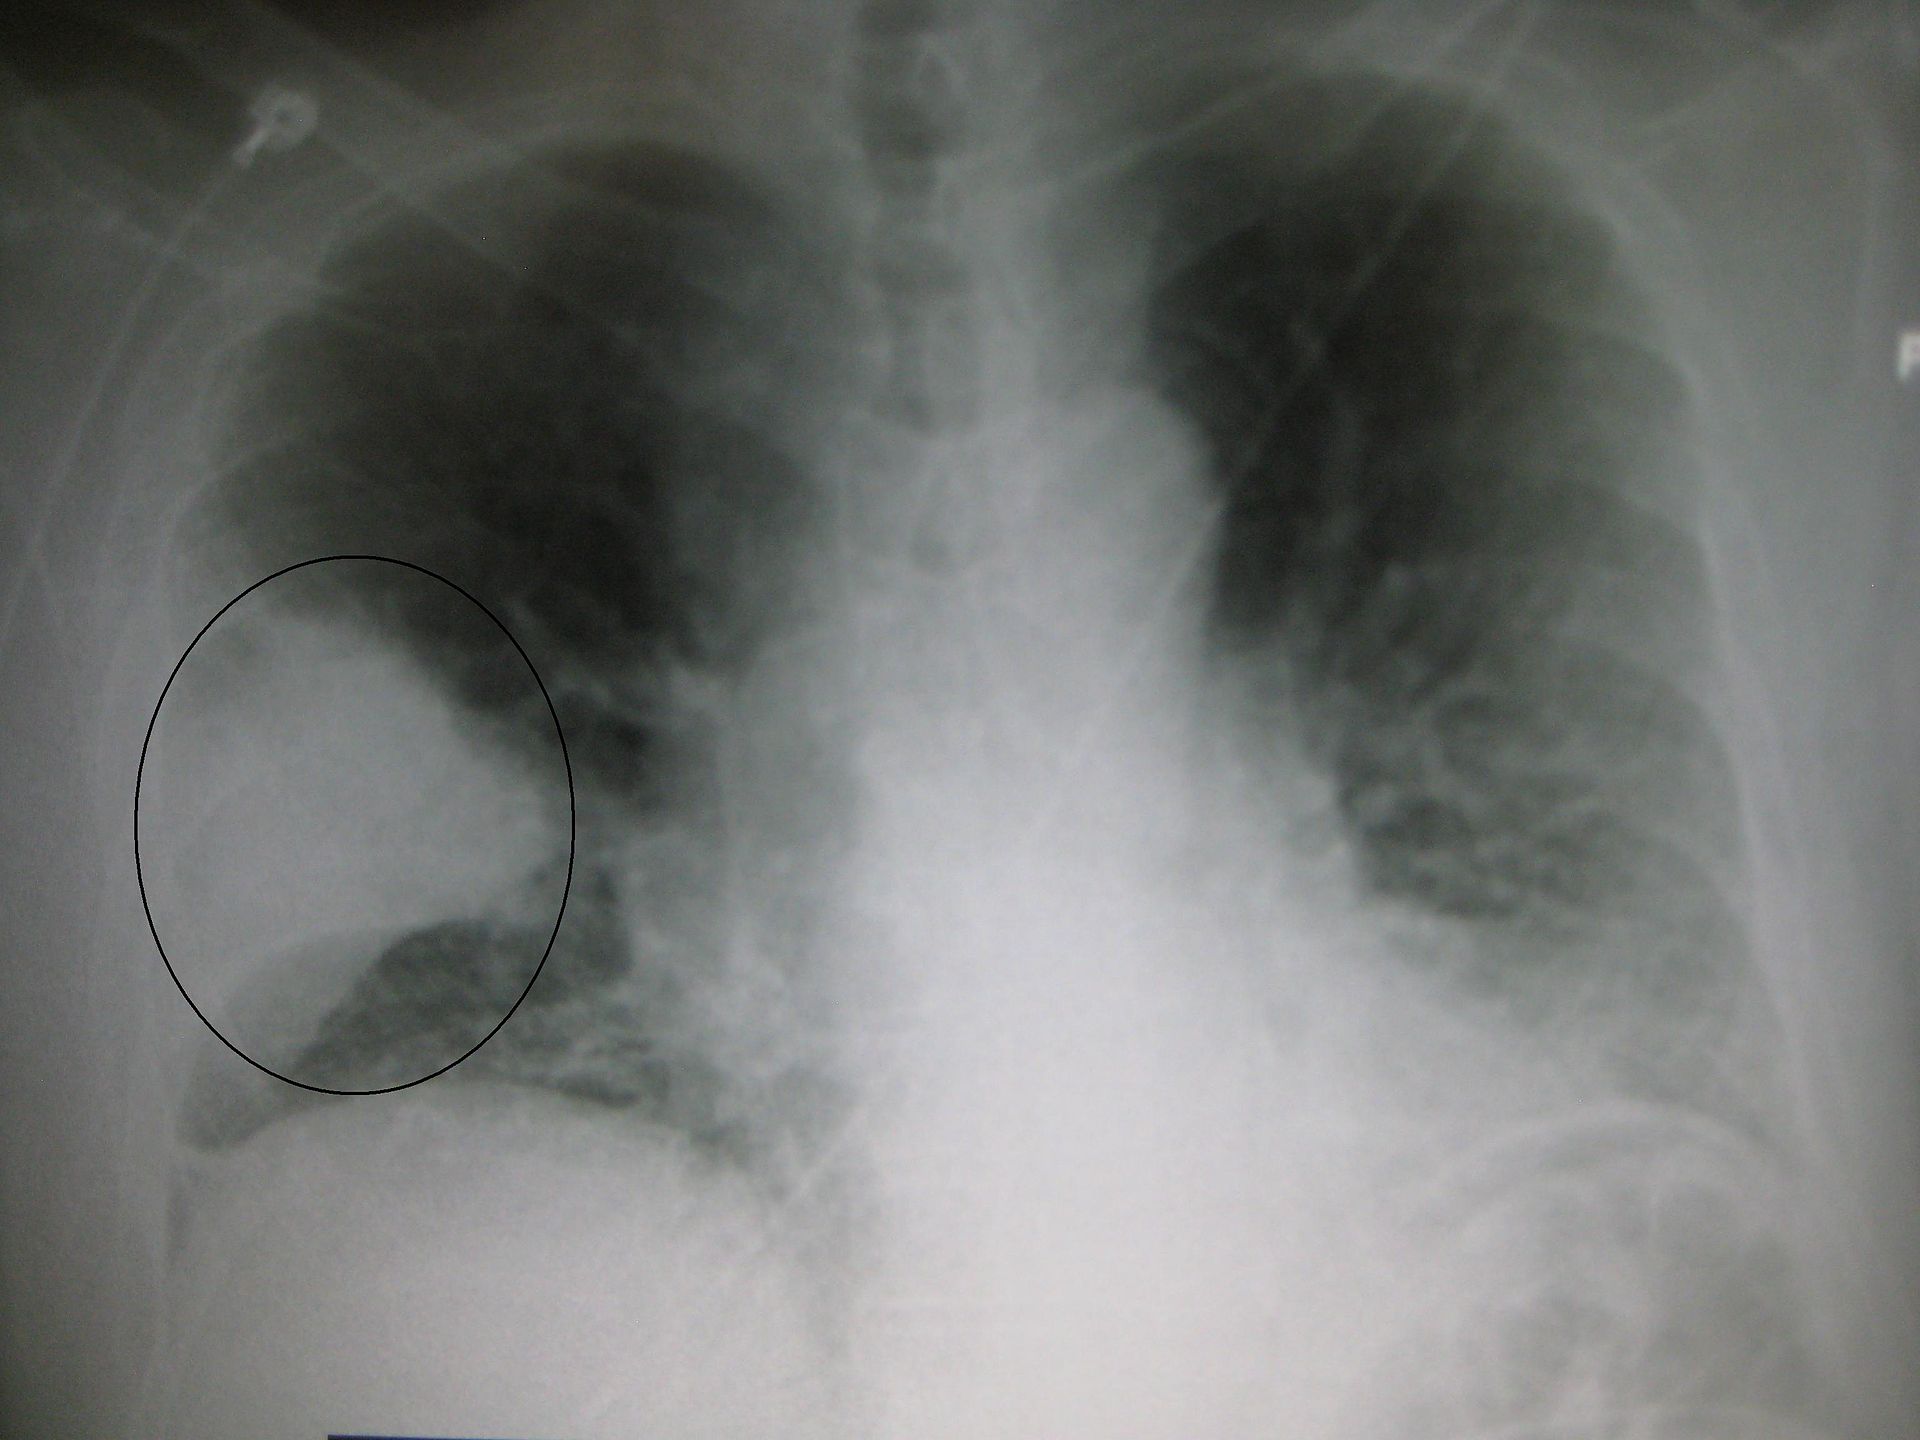

This extra image is an abnormal chest x-ray demonstrating a finding from Abnormal Chest X-Rays Part I. Can you guess what it is?

It’s pneumonia! The circle surrounds a wedge-shaped area of airspace consolidation indicative of acute bacterial lobar pneumonia (i.e., the circled lobe of the lung has been infected with bacteria.)